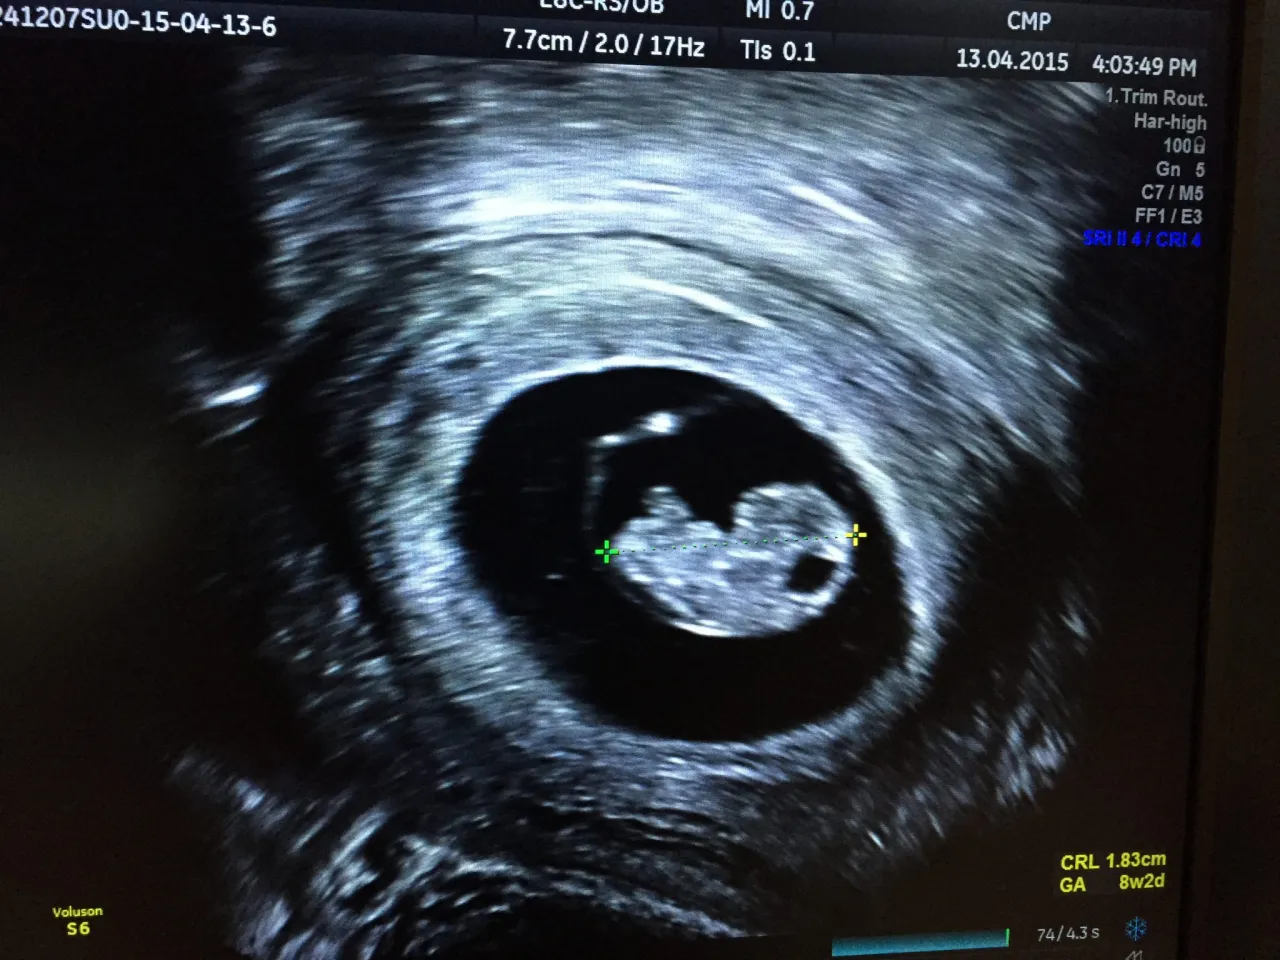

Kiedy mówimy o pierwszym USG w ciąży, musimy rozróżnić dwie kluczowe daty. Mamy tak zwane wczesnociążowe USG, które wykonuje się zazwyczaj między 6. a 10. tygodniem ciąży, oraz USG I trymestru, które zgodnie z rekomendacjami Polskiego Towarzystwa Ginekologów i Położników (PTGiP) powinno odbyć się między 11. a 14. tygodniem ciąży. To drugie badanie jest obowiązkowe i ma kluczowe znaczenie diagnostyczne, a ja zawsze podkreślam jego wagę.Często spotykam się z pytaniem, czy warto spieszyć się z badaniem USG już w 5. tygodniu ciąży. Moje doświadczenie podpowiada, że zbyt wczesna wizyta może przynieść więcej stresu niż spokoju. Przed 6. tygodniem ciąży obraz USG może być jeszcze na tyle niejednoznaczny, że nie uwidoczni zarodka ani akcji serca, co może prowadzić do niepotrzebnego niepokoju. Pamiętajmy, że kluczowe diagnostycznie, dające najwięcej informacji o rozwoju maluszka, jest badanie w 11-14 tygodniu.

Wiek ciąży wstępnie obliczamy od daty ostatniej miesiączki, ale to właśnie USG, szczególnie na etapie I trymestru, pozwala na niezwykle precyzyjne określenie wieku ciążowego na podstawie pomiaru długości ciemieniowo-siedzeniowej (CRL). To kluczowa informacja dla dalszego prowadzenia ciąży i ustalenia terminu porodu.

- Wstępna ocena wieku ciążowego na podstawie pomiaru CRL.

Zazwyczaj bicie serca płodu można zobaczyć w USG dopochwowym około 6. tygodnia ciąży. Jego obecność jest dla nas, lekarzy, najważniejszym potwierdzeniem żywotności ciąży. To moment, który często przynosi ogromną ulgę i radość przyszłym rodzicom.